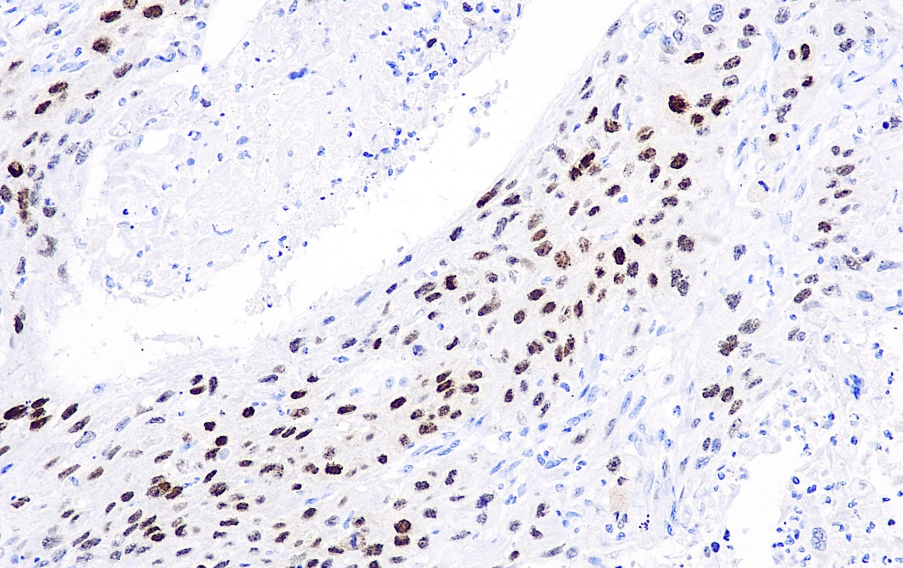

Cellular localization: nucleus

Positive control: Esophageal squamous carcinoma/neuroglioma

SOX-2 is a novel oncogene that not only participates in the early stages of tumorigenesis but is also associated with tumor cell migration, invasion, and metastasis. The expression of SOX-2 is correlated with the prognosis of various tumors, including ovarian cancer, breast cancer, head and neck tumors, lung squamous cell carcinoma, and germ cell tumors. It has been reported that the combination of SOX-2 and P63 can specifically detect over 90% of lung squamous cell carcinomas. In cervical tissue, SOX-2 expression is closely associated with HPV infection and is related to the progression of cervical hyperplasia.

The SOX-2 antibody reagent specifically binds to the SOX-2 molecular antigen. The immunohistochemistry kit containing the SOX-2 antibody reagent is suitable for the auxiliary diagnosis of lung squamous cell carcinoma.